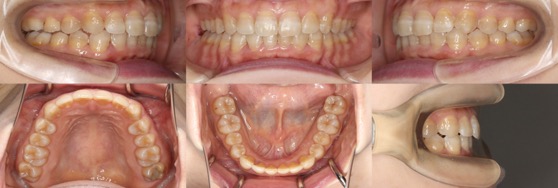

為您介紹隱適美矯正的治療案例。

※案例圖片著作權:隱適美醫師網(禁止轉載)

從案例照片的矯正前後對比中,可以清楚地看出其效果。